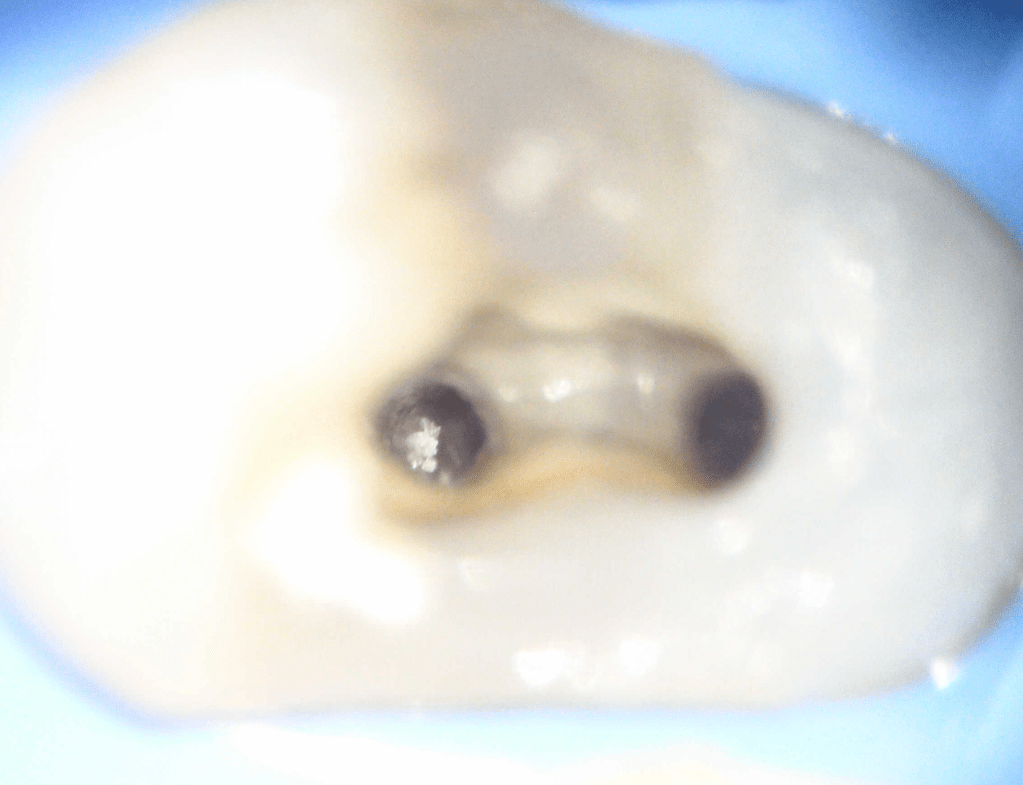

Pulpotomía biodentine + reco preendio